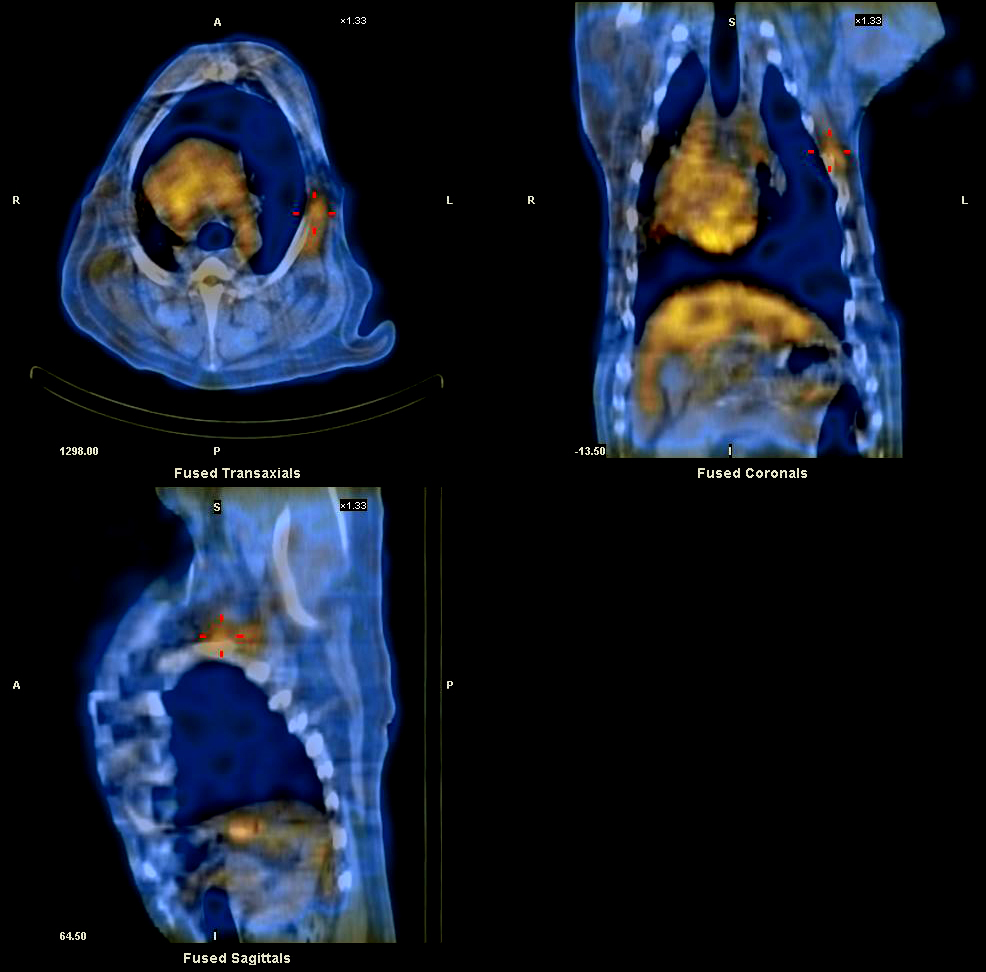

北里大学獣医学部の附属小動物診療センターにおいて、わが国で初となる犬と猫のための「核医学施設」がオープンし、PET診断が実施できるようになった。“動物に優しいがん治療”など、新たな動物医療技術の開発を目指しており、国際的にも先進的な獣医療施設になることが期待されている。

青森県十和田市にキャンパスがある北里大学獣医学部の附属小動物診療センターにおいて、わが国初となる犬と猫のための「核医学施設」がオープン。PET診断が実施できるようになった。

同大獣医学部では、今回の省令改正と同時に青森県に届出を行い、青森県と農林水産省の施設検査を受けた。同大では、すでに動物を対象とする「高精度放射線治療装置」を用いたがん治療を実施しているが、今回の核医学施設の稼働によって、がんの早期診断と放射線治療による“動物に優しいがん治療”など、新たな動物医療技術の開発を目指す。

欧米ではすでに獣医療における核医学は一般的となっているものの、PET診断と高精度放射線治療を併せて実施している施設はほとんど存在しない。同大の試みは国際的にも先進的なものになると思われる。